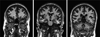

Fig. 1

Coronal diffusion weighted brain imaging in a patient with acute respiratory distress syndrome during intensive care unit hospitalization. The scan on the left shows a hyperintense area in the right frontal lobe white matter. The middle scan shows hyperintense areas in bilateral posterior frontal lobes, temporal lobes, and deep white matter tracts. The right scan shows hyperintense areas in the bilateral posterior temporal and parietal lobes and in the left cerebellum.